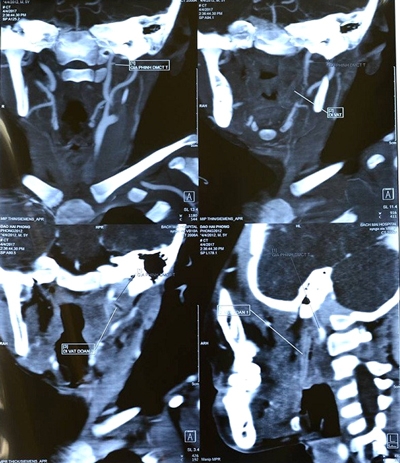

Nạn nhân Goh Chieh Ting, 25 tuổi, đang mang thai 6 tháng |

Sự việc xảy ra tại Jurong West, Singapore tuần qua. Nạn nhân được xác định là Goh Chieh Ting (25 tuổi), đang mang thai 6 tháng.

Cô Ting bị xe tải đâm khi đi sang đường. Mặc dù đã được cấp cứu tại bệnh viện, nhưng thai phụ trẻ không qua khỏi và được thông báo tử vong cùng ngày.

Tuy nhiên, các bác sĩ tại bệnh viện nơi cô cấp cứu nhanh chóng phẫu thuật khẩn cấp, cứu thành công thai nhi. Hiện, bé gái đang trong tình trạng sức khỏe ổn định.